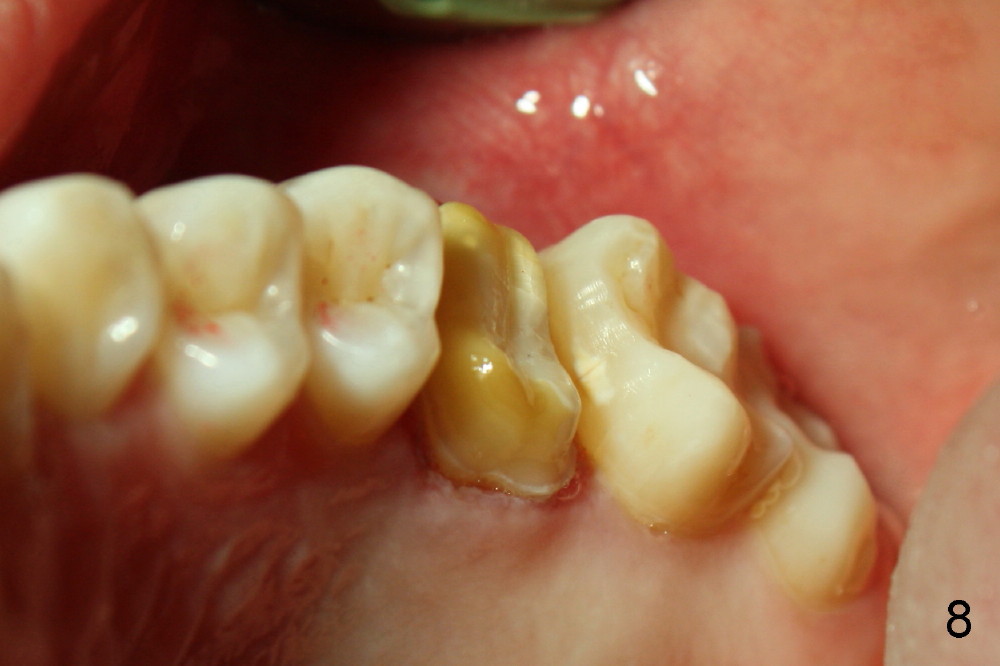

两周后,右下牙冠粘固,稍微调合,牙冠合面就穿孔了,向病人赔礼道歉,只好再预约重做,病人不满意的地方是牙冠与邻牙之间食物坎塞,重做牙冠还可能不能解决问题,只有矫正才能改变牙齿位置,倾斜度,而改正牙齿之间接触关系。不过先做左上,左下牙冠,制作也不容易,图六显示术前左上第一磨牙(*),好像supraeruption不厉害,但是咬合观显示左上第一磨牙的确往下移动不少(图七),星号(*)代表左下临时牙冠。没有任何其它选择,只好大刀阔斧磨左上第一磨牙(图八),这次大刀阔斧心情可不好,很辛苦。检查咬合,发现上下空间太大了(图九箭头),上次磨下颌基牙时太过分了。